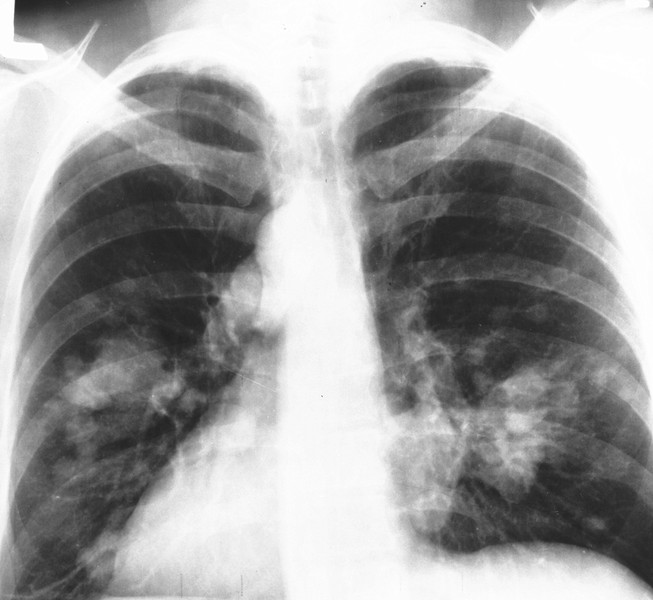

國衛院群體健康科學所長熊昭指出,國內女性罹患肺癌的危險因子,主要包括肺結核、二手菸及烹煮油煙。(photo by維基百科)

【台灣醒報記者李昀澔台北報導】二手菸及烹煮油煙,仍是國內女性罹患肺癌的「兇手」之一。國衛院群體健康科學所長熊昭20日出席「健康高峰論壇」時表示,國內女性肺癌患者逾9成都不吸菸,主要致病因素為家族病史、肺結核、二手菸及烹煮油煙。